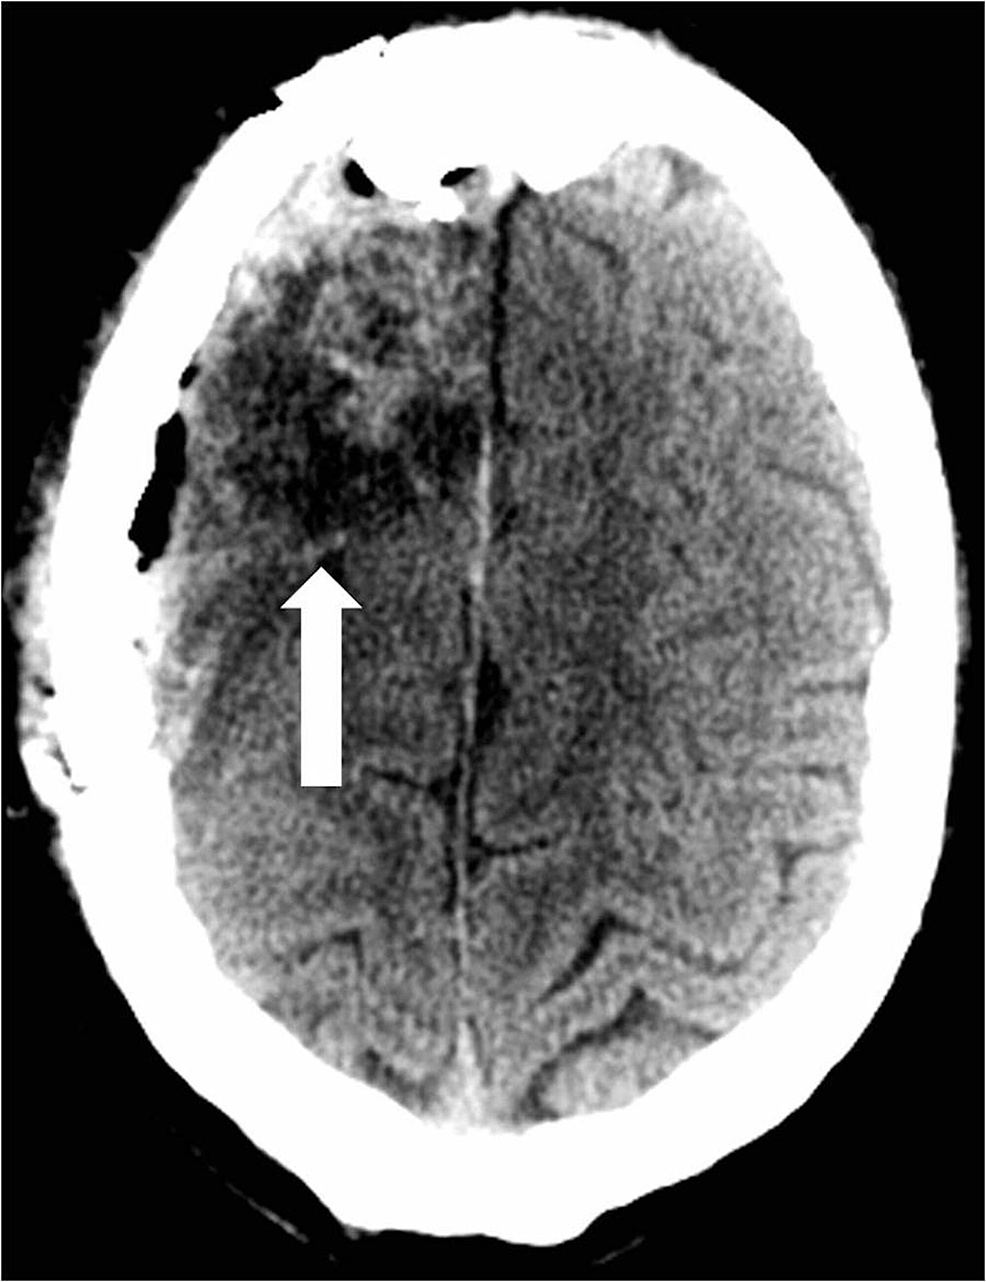

A 26-year-old male with a history of seizures presented to an outside hospital (OSH) with a new onset seizure. The patient denied drinking alcohol or recreational drug abuse. He became more alert by the time he arrived at the OSH. Besides the initial seizure and a left frontal scalp hematoma secondary to seizure-related trauma, the patient was otherwise asymptomatic. He was initially treated with phenytoin. Computed tomography (CT) of the head at the OSH showed an AVM that involved the right frontal lobe roughly measuring 4.8 cm by 6.3 cm (Figure 1).

He was then transferred for a higher level of care to a high-volume Comprehensive Stroke Center. Cerebral angiography showed a non-ruptured left frontal AVM that was fed by anterior and middle cerebral artery branches (Figure 2).